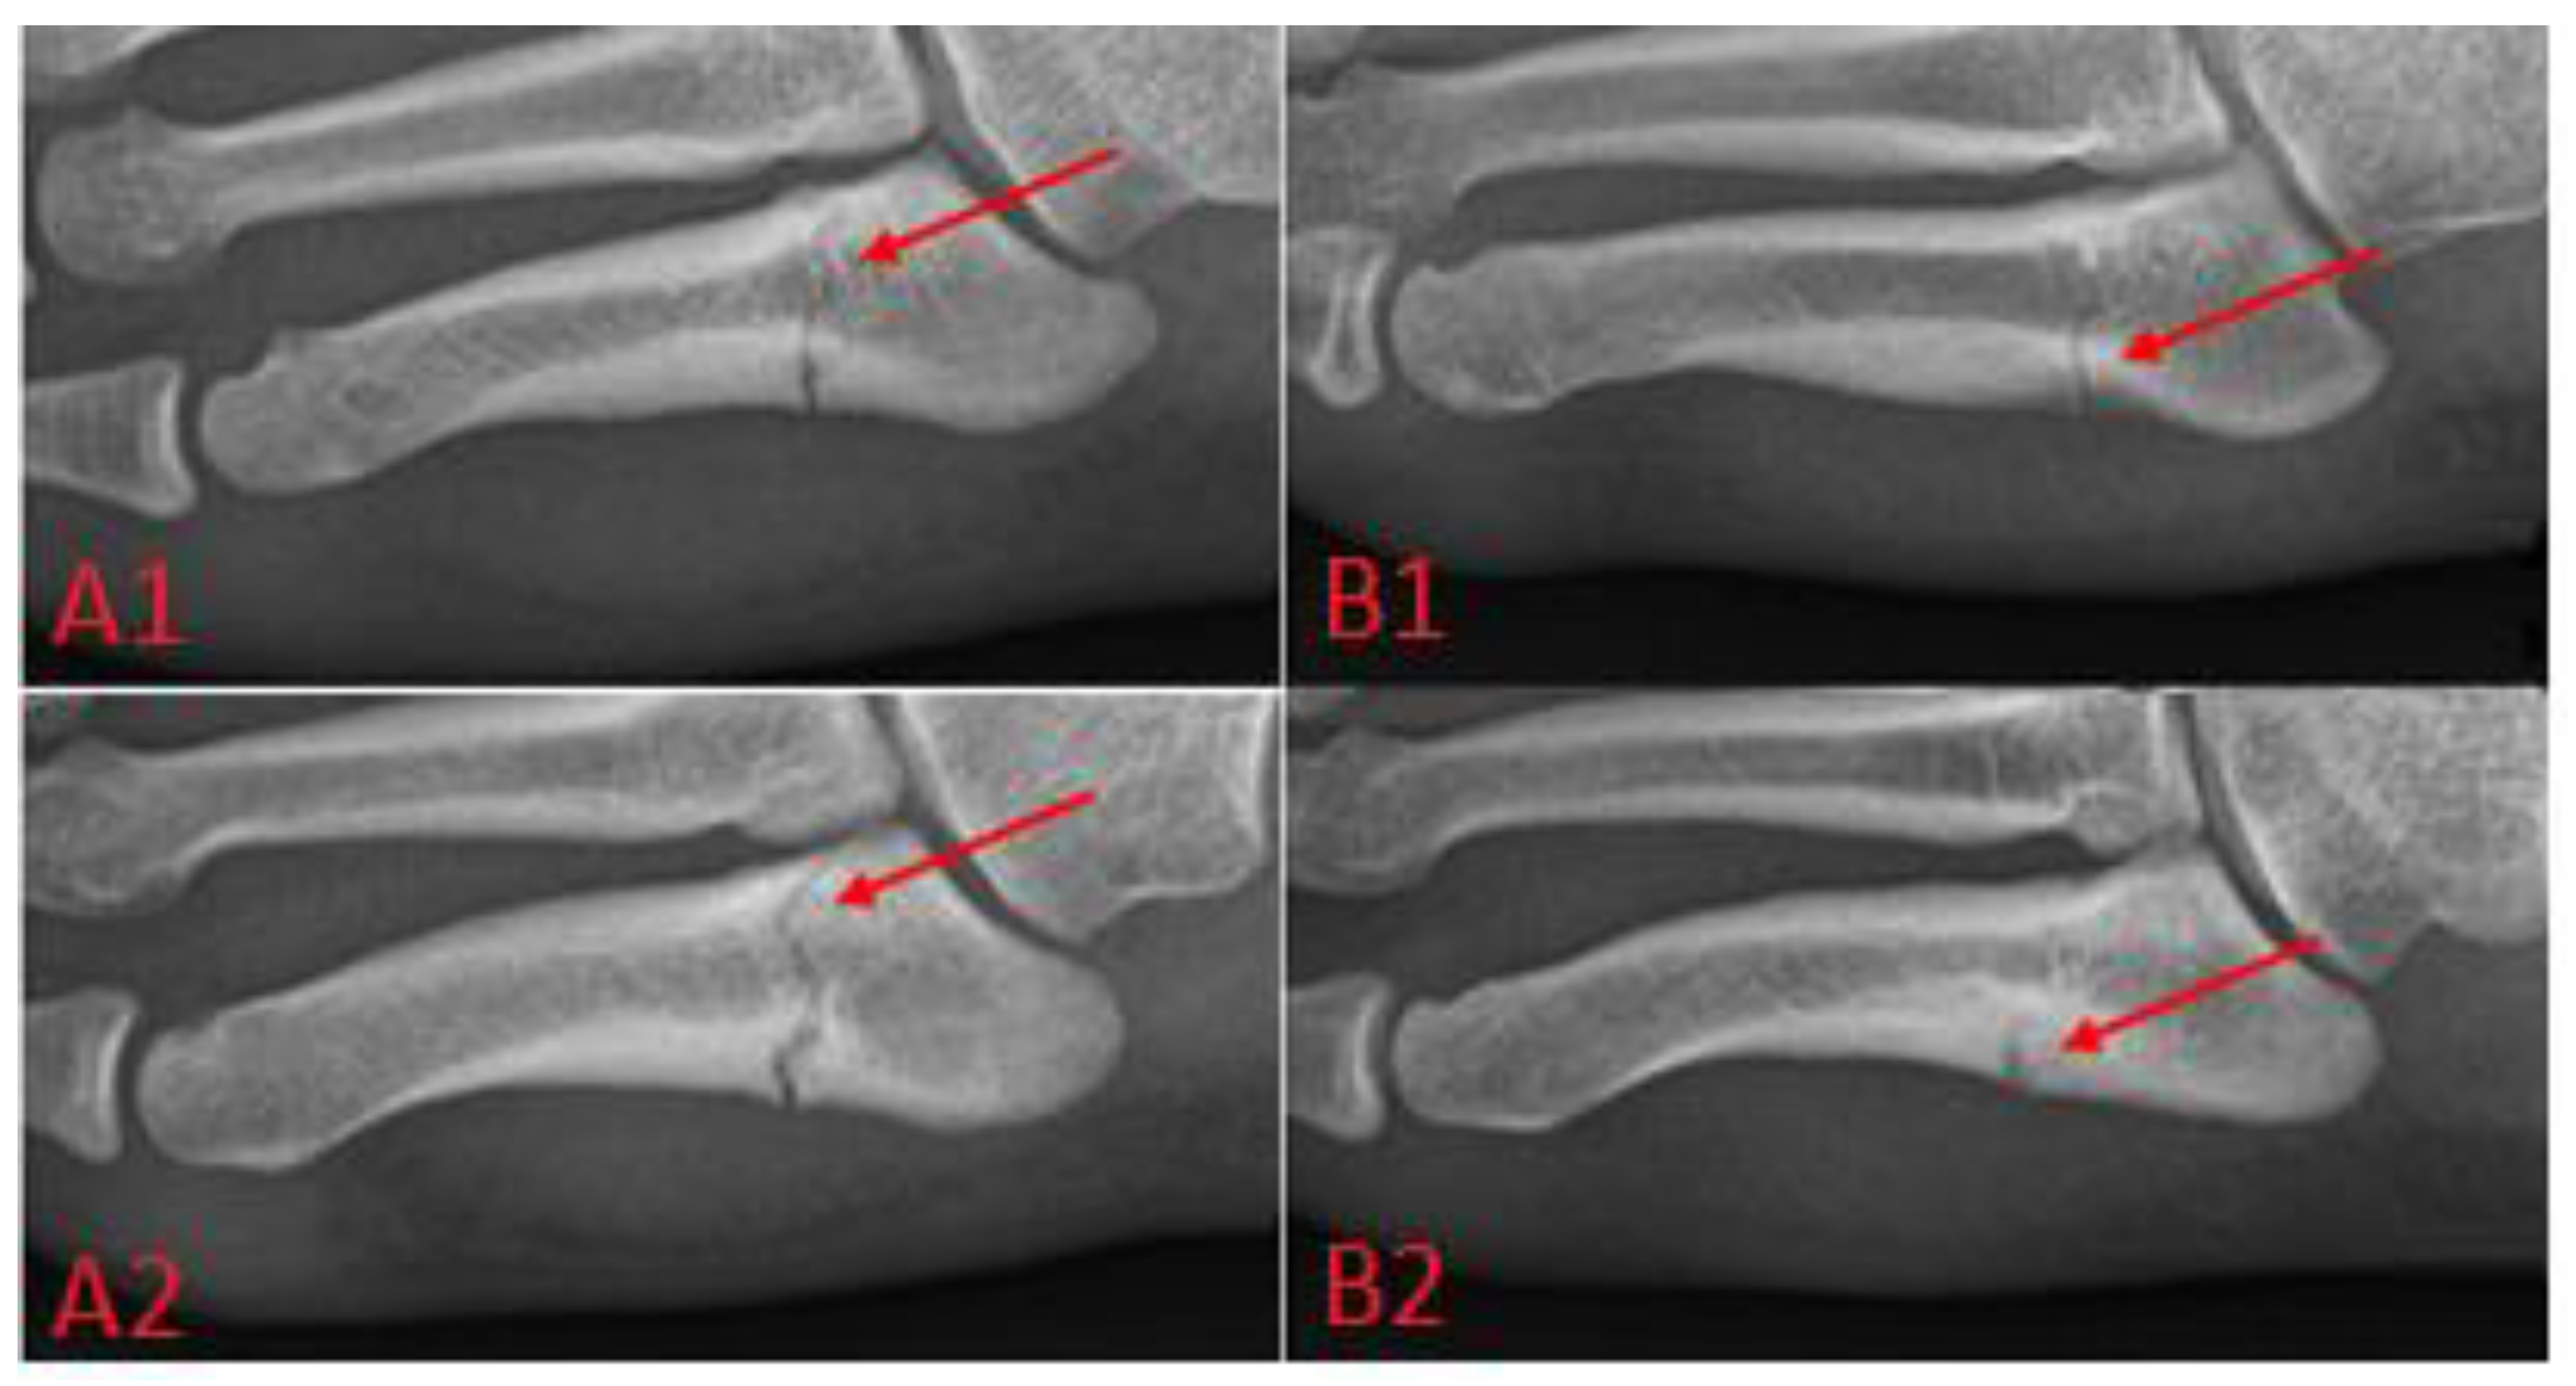

Metatarsal fractures, see Figure 3, can be treated surgically or conservatively; this paper focuses on the headless screw technique, in which the fracture is immobilized by the screw thanks to the differential pitch of the threads at the threaded ends, which leads to pulling the bone fragments together and, subsequently, to healing.

Figure 3.

New classification of the proximal 5th metatarsal fractures, according to K. T. Lee: (A1) acute complete fracture, (A2) chronic complete fracture, (B1) incomplete fracture below 1 mm, (B2) incomplete fracture of 1 mm or more.